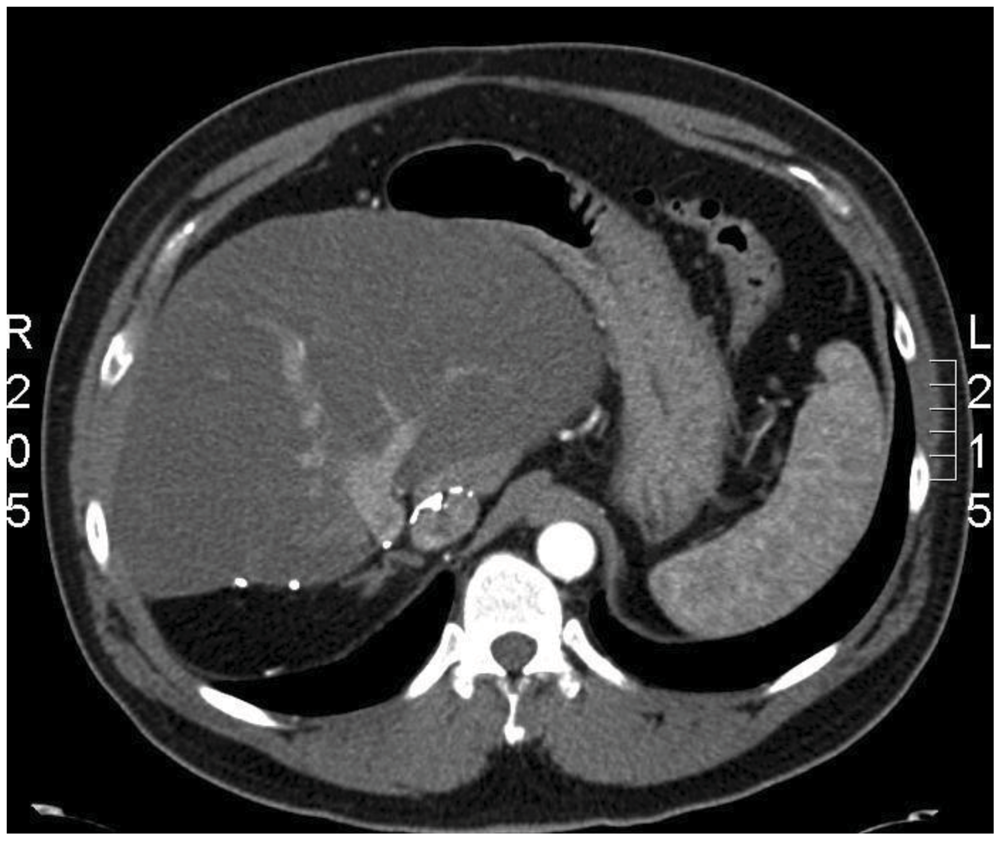

Primary Hepatic Gastrinoma Causing Zollinger-Ellison Syndrome: A Rare and Challenging Diagnosis

2. Case Report